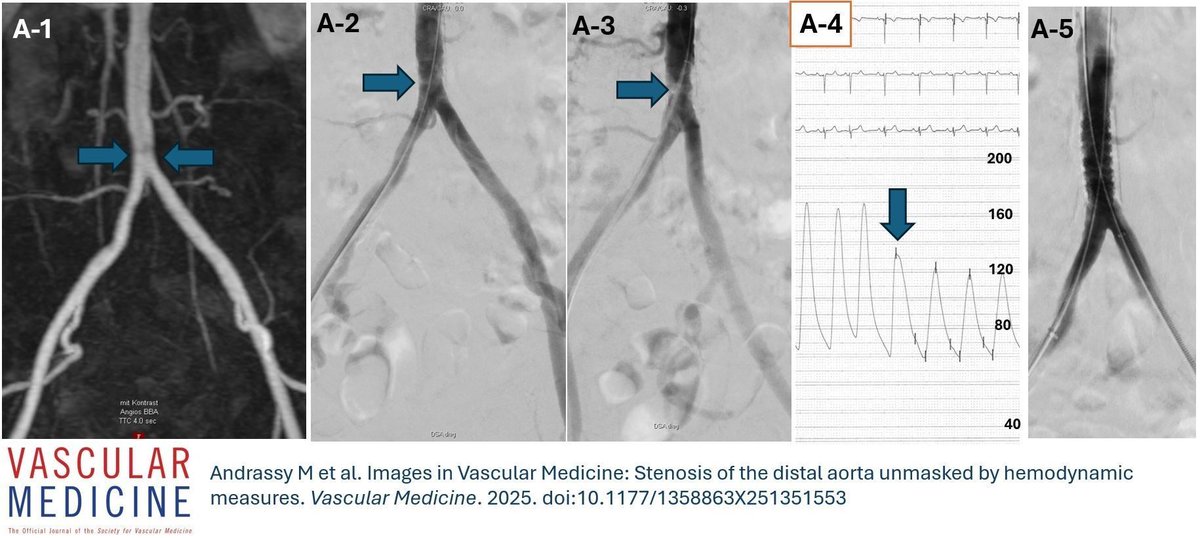

Online First! Andrassy, @EricSecemskyMD, and @gkorosoglou present a striking #ImagesInVascMed case of distal aortic stenosis—missed on cross-sectional MR angiography but revealed by invasive angiography and hemodynamic assessment. 🔗 https://t.co/EuZuoeqPoI

#PAD